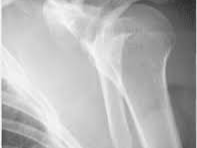

어깨뼈(견갑골) 골절의 통증, 얼마나 오래갈까?

어깨뼈 골절은 생각보다 흔하지 않지만, 교통사고, 높은 곳에서의 추락, 강한 충격 등으로 인해 발생할 수 있습니다. 어깨뼈는 인체의 비교적 두꺼운 근육층으로 둘러싸여 있어 어느 정도 충격을 흡수할 수 있지만, 일단 골절이 발생하면 회복에 오랜 시간이 걸리는 편입니다.